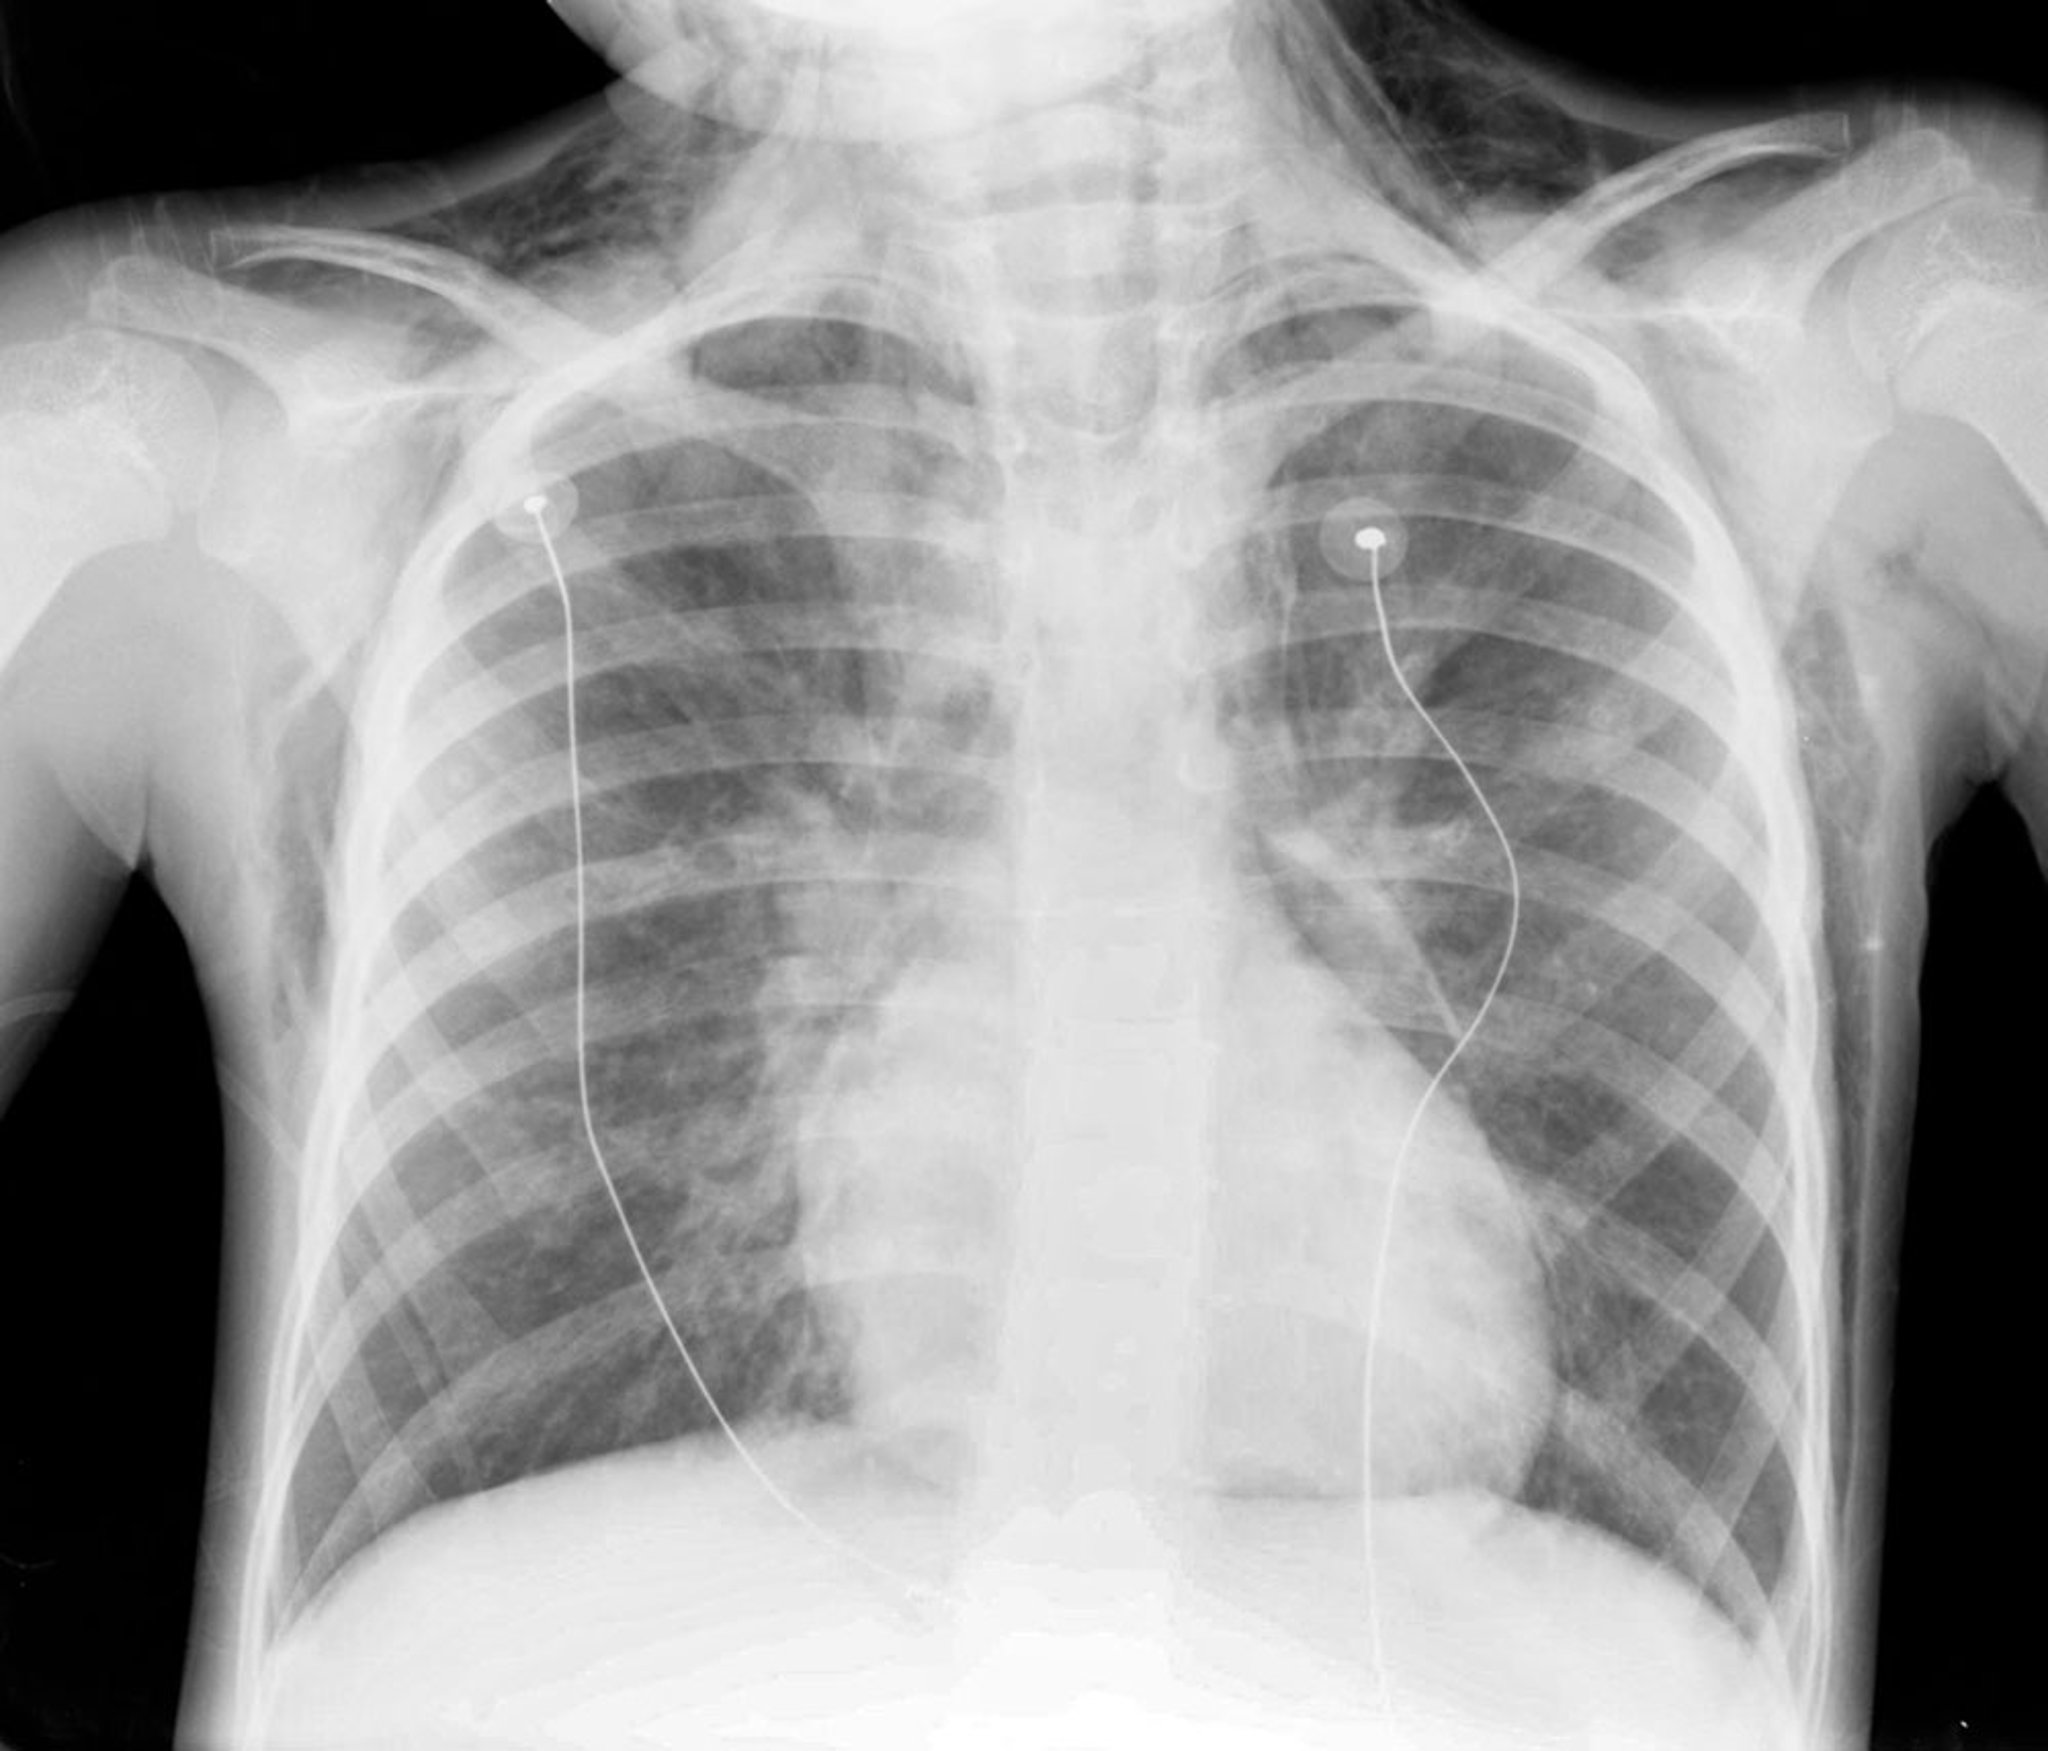

这张 X 光片显示一名儿童患有纵隔气肿。注意心脏边缘、气管周围及颈部存在气体影。